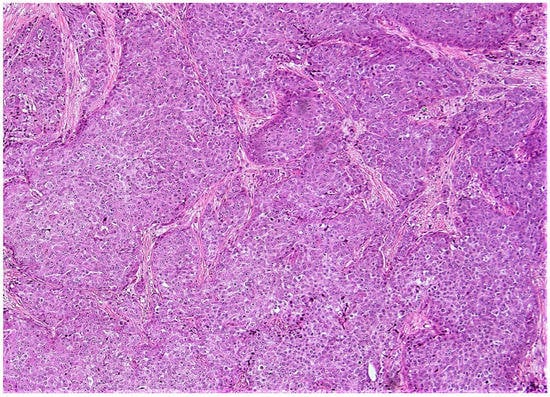

Figure 4.

(A,B) (10×): The two low risk aMMs patients considered to be high risk by ODX with a breast cancer recurrence (A) ([Supplemental Table S2—case # 1]; (B) [Supplemental Table S2—case # 2]). Note the lower grade (A) to intermediate grade (B) histologic qualities in both patients. As in (A) and (B), note the background inflammation in (A), and the somewhat cellular stroma in (B), both of which have been associated with an elevated ODX recurrence score [95].

When considering discordant patients with a very low-risk ODX and a high-risk aMMs, 15/94 (16%) very low risk ODX patients were considered to be high risk by the aMMs (Table 4 and Table S1). These patients typically had at least intermediate grade tumors (Figure 5), with relatively higher Ki-67 percentages of at least 10%, relatively lower PR H-scores, and occasionally with relatively lower ER-H scores (Supplemental Table S1). A total of 2 of these 15 discordant very low-risk ODX/high-risk aMMs patients (13.3%) had a breast cancer recurrence (Table 3 and Table S2). When considering all lower-risk ODX patients (very low and low-risk), 92/302 (12%) lower-risk ODX patients were considered to be higher-risk by the aMMs (Table 4), with 11 of these 92 lower-risk ODX/high-risk aMMs discordant patients (12%) having a breast cancer recurrence (Table 3 and Table S2). When examining the histology of these eleven lower-risk ODX/high-risk aMMs patients that recurred, they typically had at least intermediate grade tumors (Figure 6), often with higher Ki-67 percentages of at least 20%, relatively lower PR H-scores, and occasionally relatively lower ER-H scores (Supplemental Table S1).